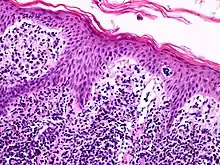

![]() A histological view of Lutzner cells surrounded by erythrocytes in a blood smear. | |

Lymphocytes are white blood cells that form from a blood stem cell, hemocytoblast, in bone marrow and travel to other parts of the body, normally specific lymphoid tissues, to mature. After being produced, the stem cell differentiates into lymphoid stem cells. Then, T-lymphocytes further mature and differentiate into lymphoblasts when the hormone thymosin is secreted from the thymus. Finally, specialized immune cells, B cells and T cells, and nonspecialized immune cells, nature killer cells, are created from the lymphoblasts. This process is referred to as Leukopoiesis. Lutzner cells are an atypical form of T-cell lymphocytes and are normally CD4+.[3] Lutzner cells develop because of clonal gene rearrangements in the T-cell receptor or antibody. This rearrangement occurs early in the differentiation process and creates novel T-cell receptors that mimic the structure of normal antibodies but are not able to function properly. This mutated form contains an enfolded nuclear membrane and has a cerebriform shape, resembling the shape and folds of the brain.[5] Lutzner cells can be best seen through electron microscopy because it is able to show the 3-D structure of the cell.

Lutzner cells are bigger than normal lymphocytes and contain extensive folding in their membrane. They are described at being cerebriform in shape, and can be diploid or tetraploid. It also contains a large nucleus with a minimum cytoplasm. Lutzner cells are more predominant in Mycosis Fungoides, but are also found in Sézary Syndrome.[7]